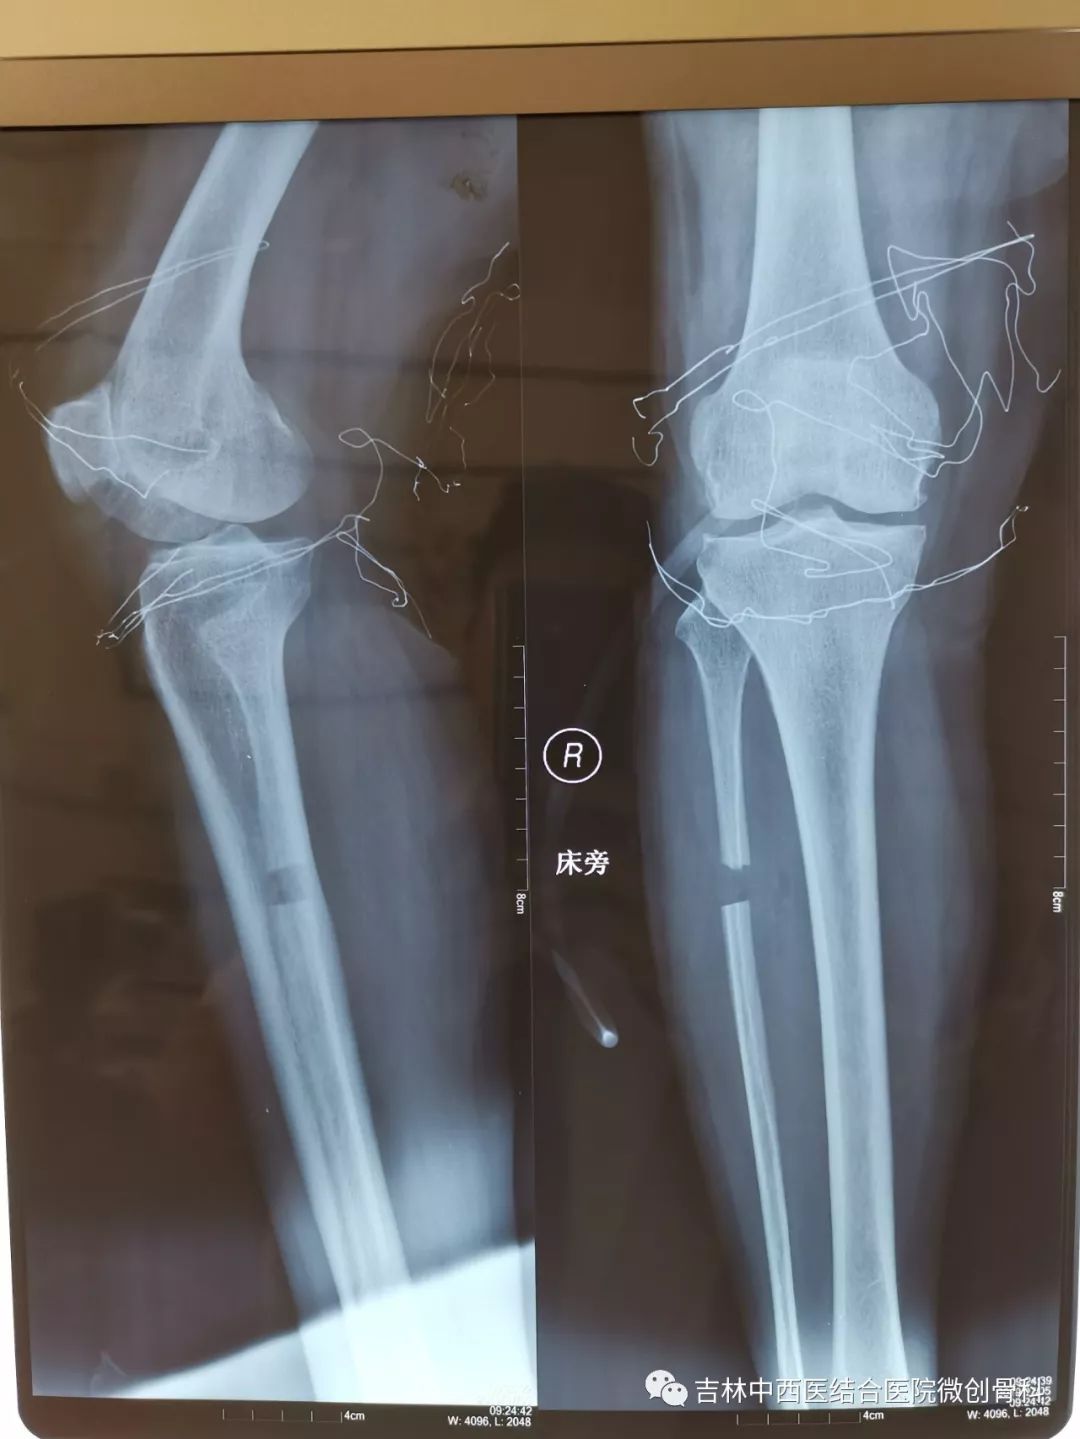

内翻膝胫骨近端高位截骨治疗